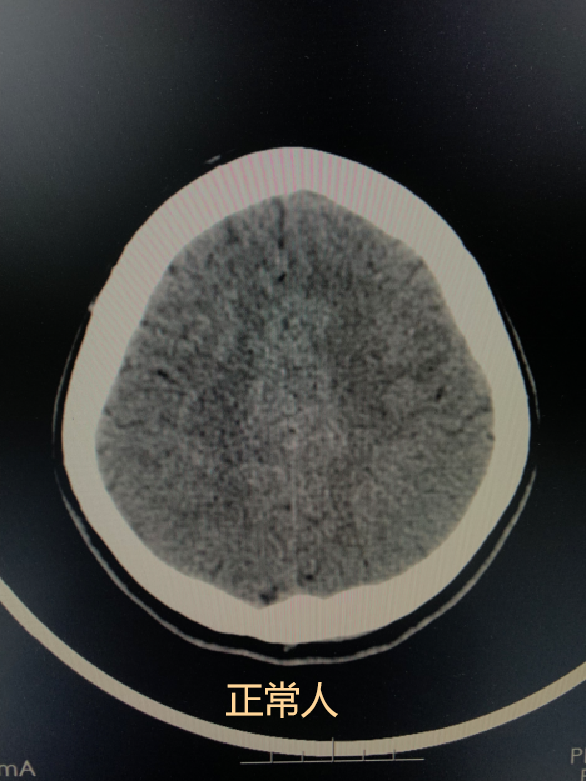

之所以排在第一位,是因为一般60岁以上人群做CT检查后经常会出现这种征象。大部分情况下它是一种生理性改变,和人老了头发会变白,会有皱纹是一个道理)

60岁体检女性。可以看到与正常人比,脑沟增宽了